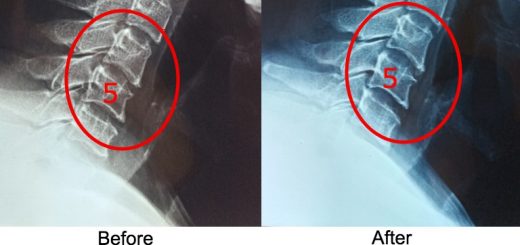

Hunching 55 year old